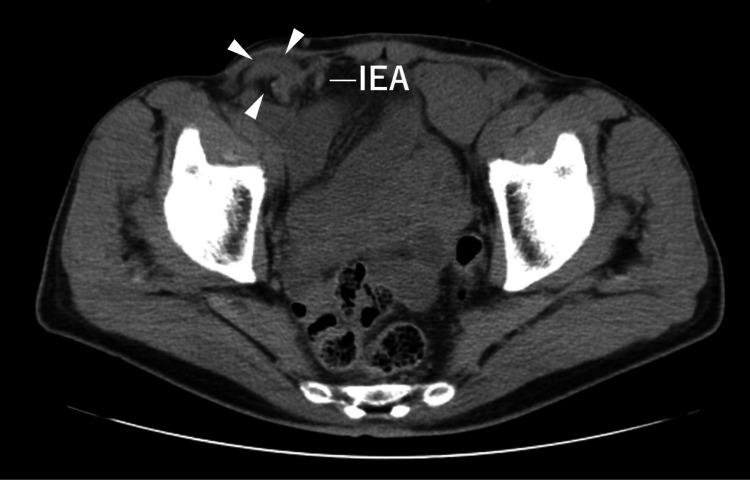

Here, we report a case of laparoscopic trans-inguinal hernia repair (transabdominal preperitoneal repair or TAPP) for a recurrent inguinal hernia following direct Kugel surgery. A 71-year-old man underwent direct Kugel hernioplasty for a right inguinal hernia at another hospital 4 years prior to presentation. The patient subsequently underwent laparoscopic surgery using the TAPP technique, during which the abdominal cavity was visualized with a laparoscope, revealing a tubular mesh protruding towards the abdominal cavity with a direct and indirect hernia ring. Three months post-surgery, no recurrence was observed.

在此,我们报告一例针对直接Kugel手术后复发性腹股沟疝的腹腔镜经腹股沟疝修补术(经腹腹膜前修补术或TAPP)。一名71岁男性在就诊前4年于另一家医院接受了右侧腹股沟疝的直接Kugel疝修补术。该患者随后接受了使用TAPP技术的腹腔镜手术,术中通过腹腔镜观察腹腔,发现一个管状补片向腹腔突出,伴有直疝和斜疝疝环。术后三个月,未观察到复发。